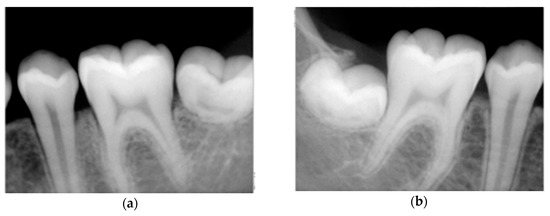

2.3. Intra-Oral Examination